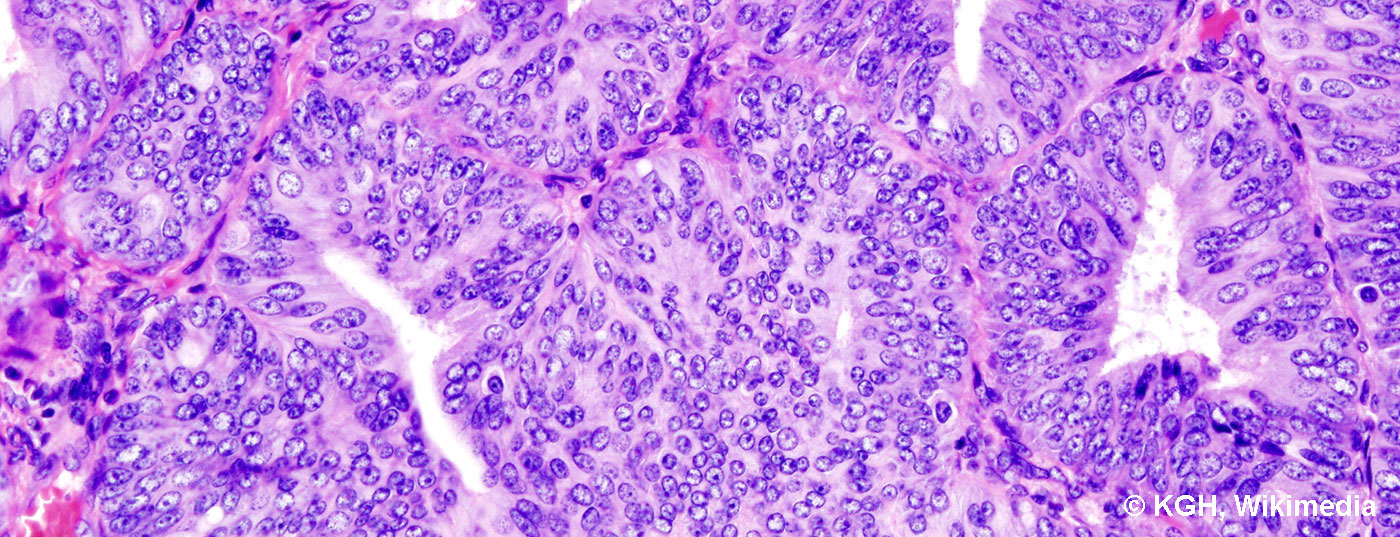

Le cancer de l’endomètre est considéré comme un carcinome de la femme âgée. Toutefois, il apparaît également à un âge plus jeune, en particulier en présence de syndromes tumoraux familiaux tels que le cancer colique héréditaire non polyposique (HNPCC ou syndrome de Lynch). On distingue deux types de carcinome de l’endomètre. Le cancer de l’endomètre de type I correspond histologiquement au cancer de l’endomètre endométrioïde, qui est associé aux œstrogènes et plutôt bien différencié, et qui présente par conséquent un pronostic plus favorable. Le facteur de risque influençable pour ce carcinome est le syndrome métabolique, en particulier l’obésité et l’hypertension. Le cancer de l’endomètre de type II correspond généralement, sur le plan histologique, à un type séreux ou à cellules claires. Il n’est pas associé aux œstrogènes et est comparable au cancer de l’ovaire en termes de pronostic et de traitement à mettre en œuvre, c’est-à-dire qu’il est associé à un pronostic nettement moins favorable. Il n’existe pas de facteurs de risque typiques pour le carcinome de type II.

L’examen histologique, qui se fait généralement par hystéroscopie et curetage, est impératif, notamment en cas de saignements post-ménopause répétés et en présence de facteurs de risque tels que l’obésité, l’hypertension, le diabète sucré, mais aussi en cas de SOP (syndrome des ovaires polykystiques), de syndrome HNPCC ou de traitement au tamoxifène (fig. 2).